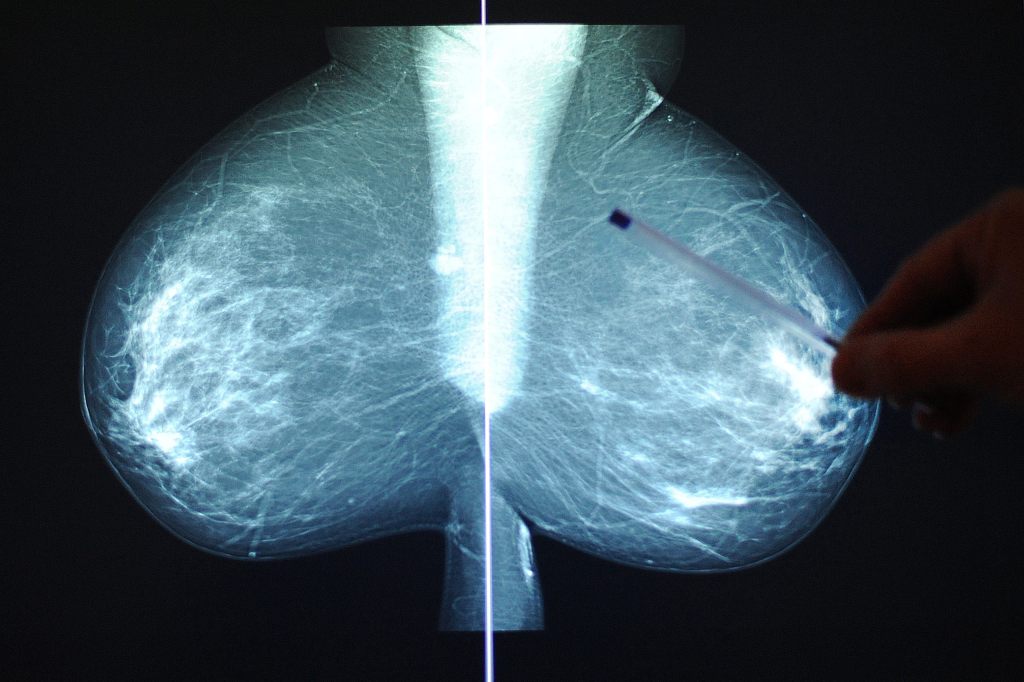

Jährlich erkranken in der Schweiz 6’000 Personen an Brustkrebs. Der Studienleiter Walter Weber stellt mit seiner TAXIS-Studie eine vielversprechende Alternativbehandlung in Aussicht.

Die Studie hat es sich zum Ziel gemacht, eine bessere Alternative zur herkömmlichen Brustkrebsbehandlung zu schaffen. Bislang wurden bei der Behandlung von Brustkrebs stets alle Lymphknoten entfernt. Ein Viertel aller Patientinnen und Patienten kämpften infolge einer solchen Behandlung mit beträchtlichen Konsequenzen wie beispielsweise chronischen Schmerzen, Schwellungen des Armes (das sog. Lymphödem), Empfindungsstörungen oder auch Beweglichkeitseinschränkungen.

Damit soll jetzt Schluss sein. Weber und seine Kollegen fanden eine Methode, die für die behandelten Patientinnen möglichst wenige Nebenwirkungen mit sich bringt. Bei der TAXIS-Methode werden die befallenen Lymphknoten selektiv entfernt. Im Schnitt werden somit lediglich vier, statt 15 Lymphknoten entnommen. Dies sei eine revolutionäre Neuerung, so der Arzt.